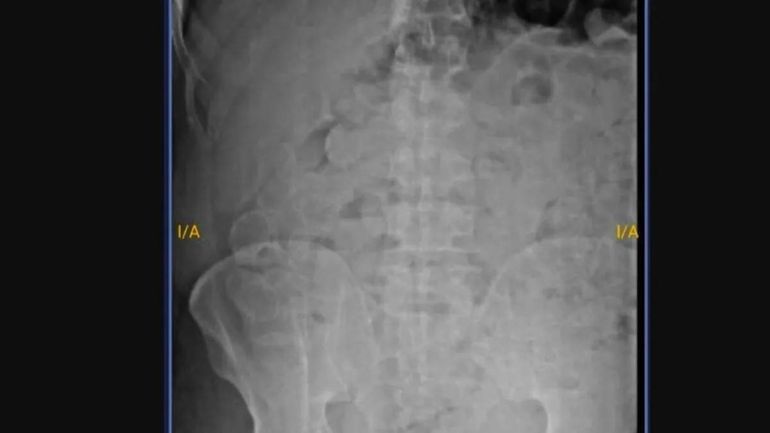

Un hecho insólito sacudió al Servicio Penitenciario de Jujuy, cuando un preso tuvo que ser hospitalizado de urgencia luego de ingerir 180 cápsulas rellenas de marihuana.

El detenido fue derivado al hospital Pablo Soria, donde el personal de salud le diagnosticó consumo de sustancia. Ante la revisión médica, admitió que había tragado decenas de cápsulas con estupefacientes durante el período en que estuvo fuera del penal, aprovechando su salida transitoria.

Tras ser derivado al hospital provincial, el paciente fue diagnosticado preliminarmente por consumo de sustancias y quedó internado bajo custodia, en observación, mientras se aguardaba la expulsión del material ingerido.

Por su parte, personal de Gendarmería concurrió al centro de salud para vigilar al reo hasta que devuelva las cápsulas para después sean analizadas en una prueba de campo y así constatar de qué estupefaciente se trata.